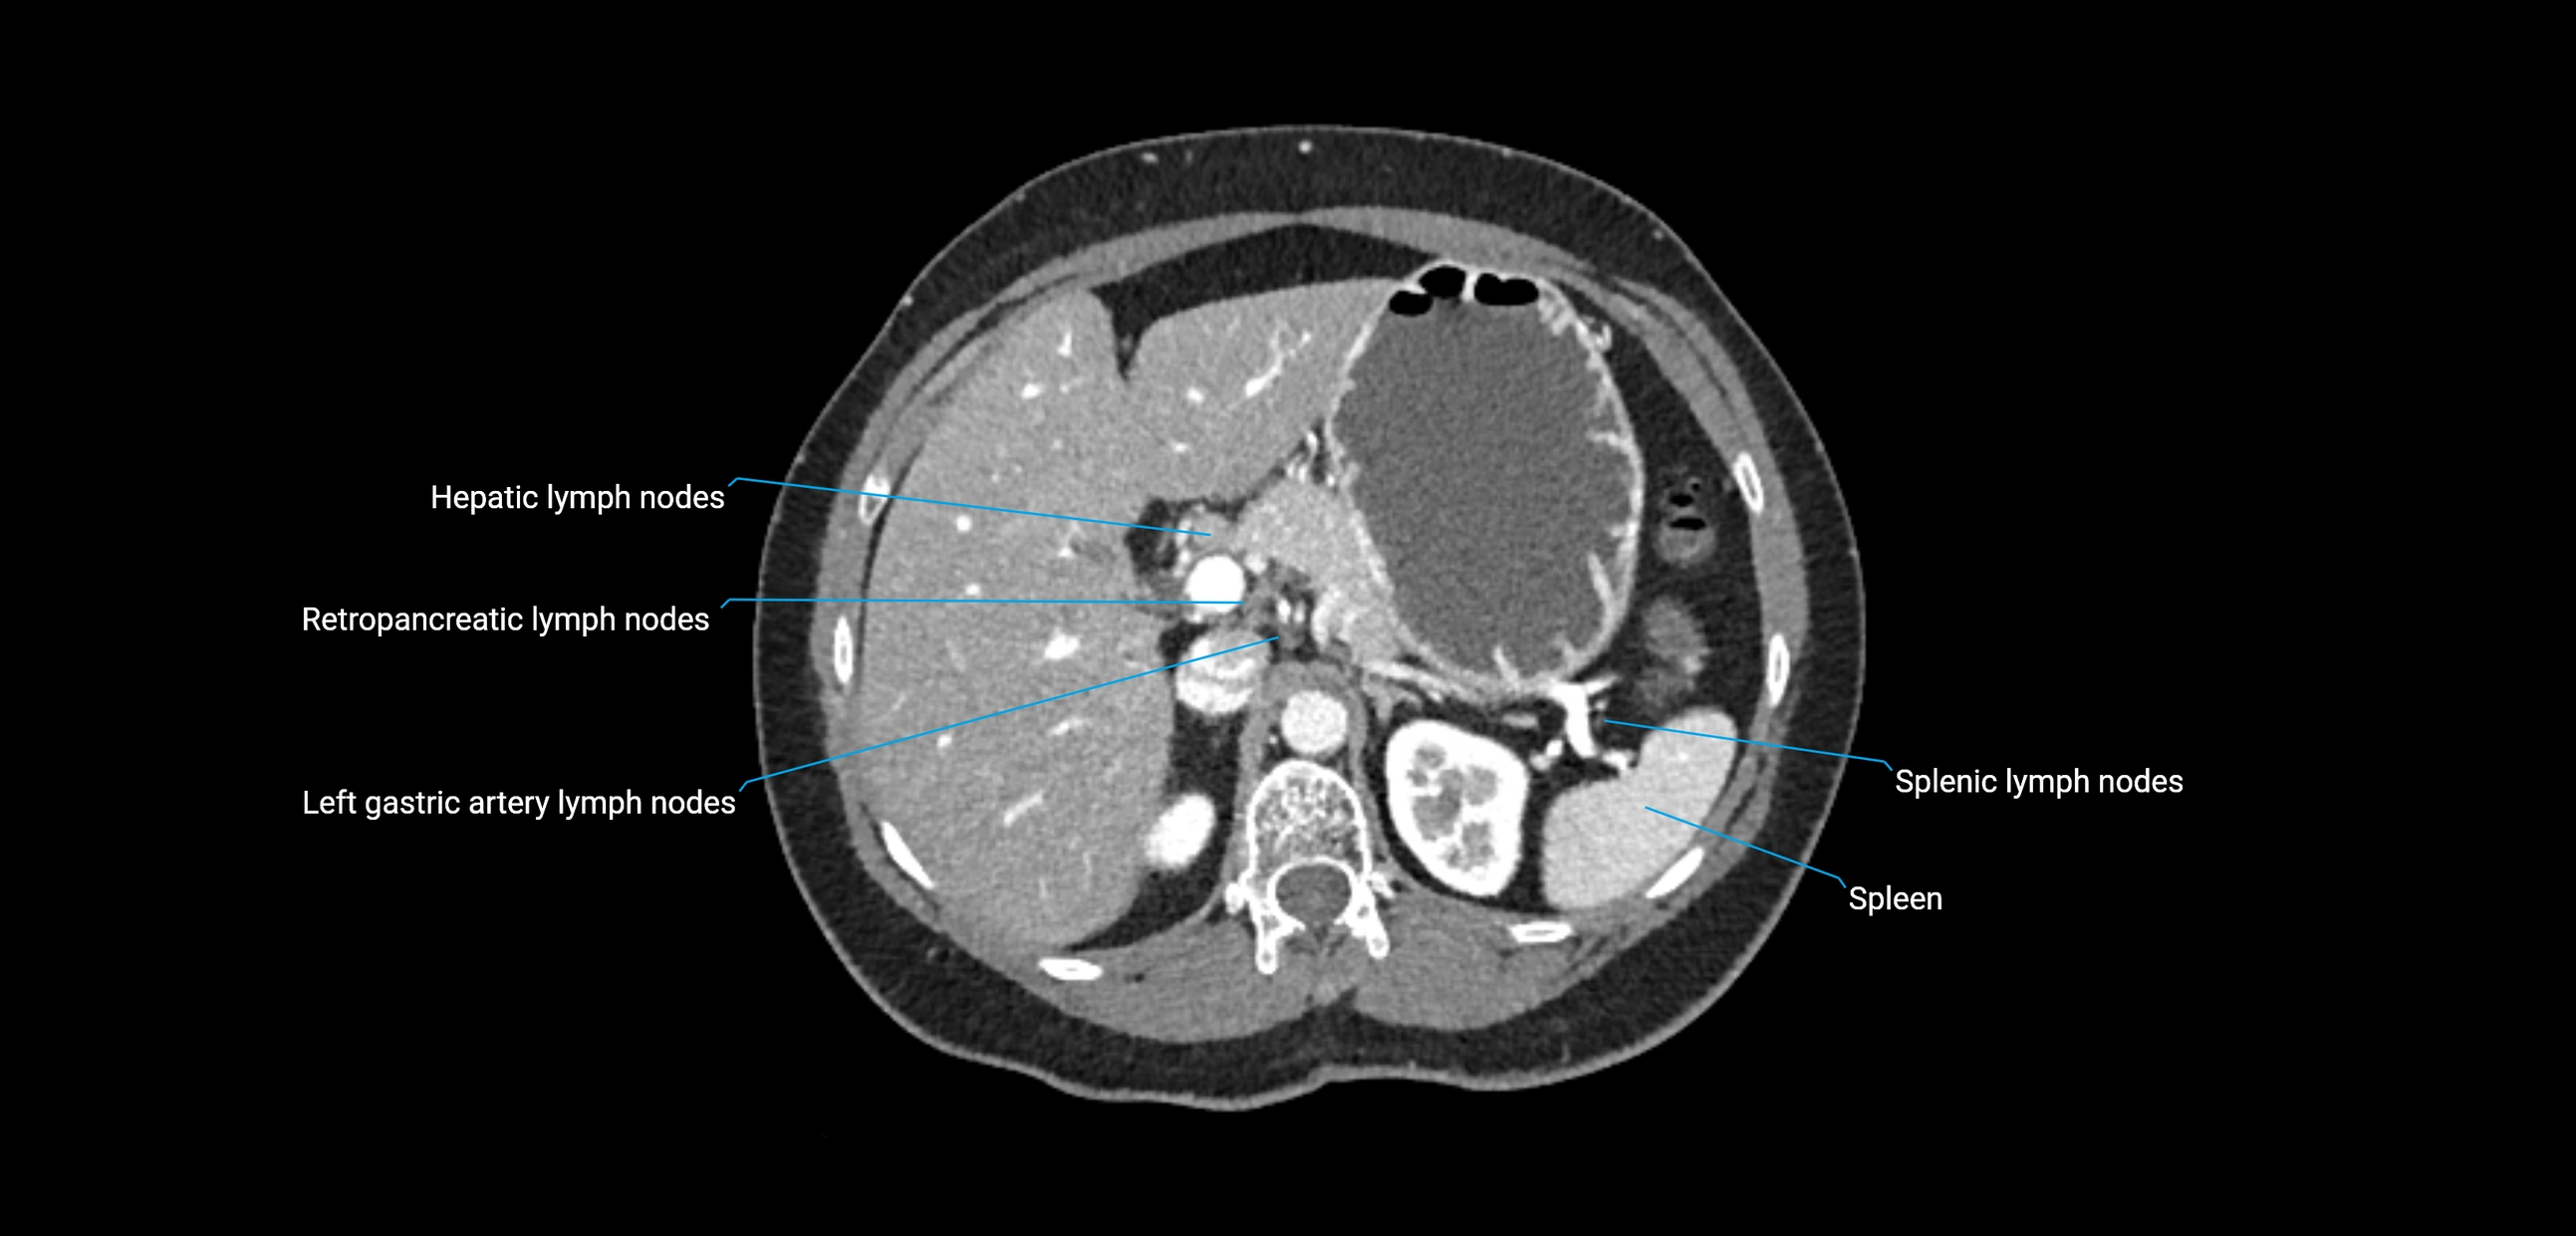

MRI images

image